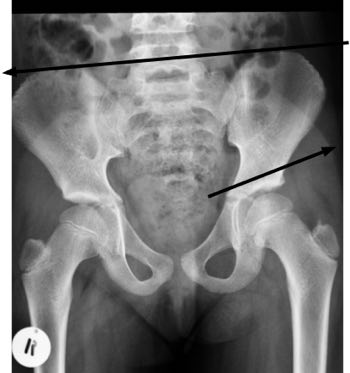

An x-ray will usually reveal what's happening in your hip

It's absolutely vital you immediately see an orthopaedist, or chiropractor who specialises in hips. An x-ray and careful evaluation are very important.